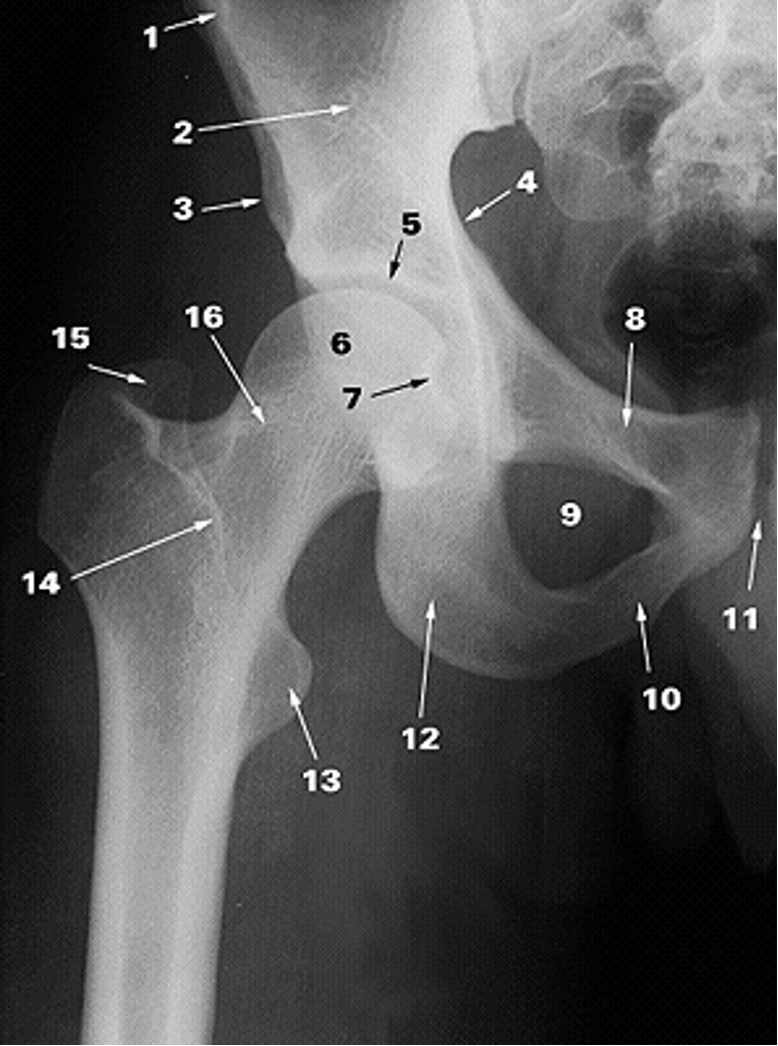

<p>1.</p>

1.

Anterior Superior Iliac Spine (2)

24

New cards

<p>2.</p>

2.

Ilium (2)

25

<p>3.</p>

3.

Anterior Inferior Iliac Spine (2)

26

<p>4.</p>

4.

Pelvic Brim

27

<p>5.</p>

5.

Acetabular Fossa (2)

28

<p>6.</p>

6.

Head of Femur (2)

29

<p>7.</p>

7.

Fovea

30

<p>8.</p>

8.

Superior Ramus of Pubis (2)

31

<p>9.</p>

9.

Obturator Foramen (2)

32

<p>10.</p>

10.

Inferior Ramus of Pubis (2)

33

<p>11.</p>

11.

Pubic Symphysis (2)

34

<p>12.</p>

12.

Ischium

35

<p>13.</p>

13.

Lesser Trochanter (2)

36

<p>14.</p>

14.

Intertrochanteric Crest (2)

37

<p>15.</p>

15.

Greater Trochanter (2)

38

<p>16.</p>

16.

Neck of Femur (2)